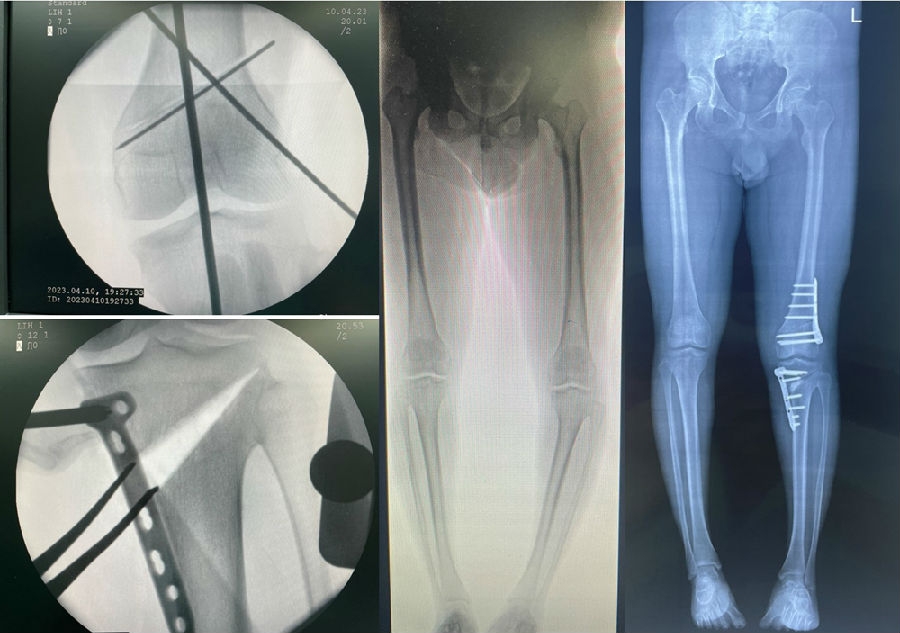

经典病例

术后影像